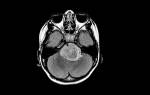

Эта операция не более опасна, чем другие хирургические вмешательства, но требует тщательной подготовки. Перед шунтированием сердца пациент должен пройти полное медицинское обследование. Это включает обязательные лабораторные анализы, ЭКГ, ультразвуковое исследование и оценку общего состояния здоровья. Также необходимо провести коронарографию (ангиографию), которая позволяет оценить состояние артерий, снабжающих сердечную мышцу кровью, а также выявить степень сужения и местоположение атеросклеротической бляшки. Исследование выполняется с использованием рентгеновского оборудования и включает введение контрастного вещества в сосуды.